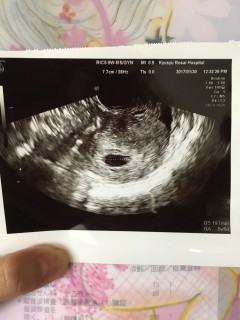

原因不明の不妊症でしたが、幸いなことに一度の体外受精にて妊娠することができました! この日心拍も確認でき、とりあえず一安心。 胎芽は1.9ミリとのこと。 この週数で心拍まで確認できるのは全体の2割程度とのことでした。 無事出産まで辿り着けるよう、頑張りたいと思います。